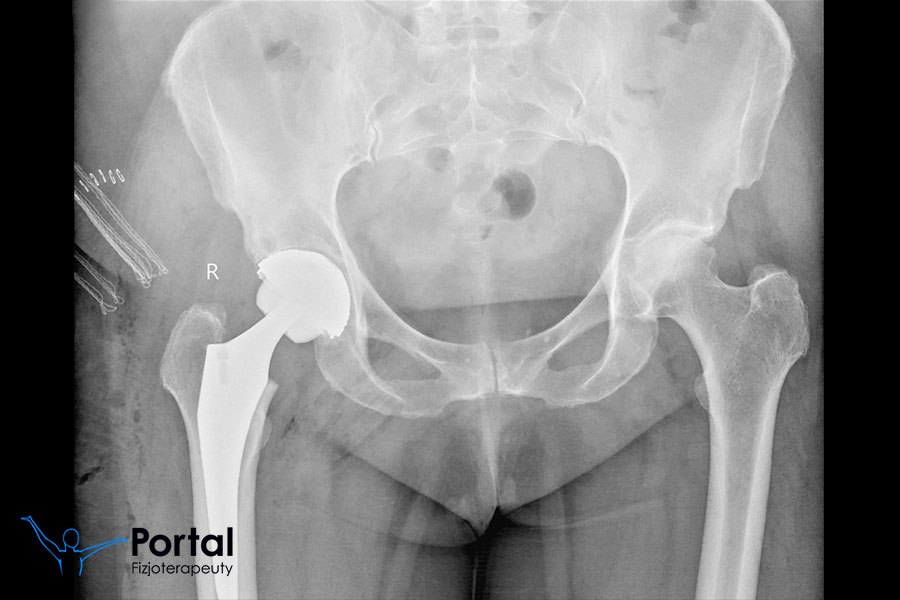

Endoprotezoplastyka to zabieg polegający na wymianie zniszczonego procesem chorobowym stawu na sztuczny, w pełni sprawny, mający przywracać biomechanikę ruchu. Najczęściej operację wykonuje się w odniesieniu do stawu biodrowego lub stawu kolanowego, zaś wskazaniem jest zazwyczaj zaawansowana choroba zwyrodnieniowa stawów.

Zabieg endoprotezoplastyki trwa zazwyczaj maksymalnie do 2 godzin i wykonuje się go w znieczuleniu zewnątrzoponowym, w efekcie czego pacjent pozostaje świadomy, lecz nie odczuwa niczego od pasa w dół. Istnieje także możliwość znieczulenia ogólnego u osób, które nie są w stanie wytrzymać tej operacji przy zachowaniu świadomości. Po zadziałaniu znieczulenia chirurg ortopeda wykonuje nacięcie skóry nad stawem (długości 10-15 cm), aby odsłonić obie powierzchnie stawowe. Następnie usuwa zniszczone i chore tkanki stawu, po czym na ich miejsce wstawia indywidualnie stworzoną endoprotezę. W przypadku endoprotezoplastyki stawu biodrowego do kanału kości udowej wprowadza trzpień protezy, a do kości biodrowej przyczepia sztuczną panewkę. Z kolei w przypadku stawu kolanowego najpierw wycina ACL (więzadło krzyżowe przednie) oraz obie łąkotki, a dopiero później zniszczone elementy stawowe. Po umieszczeniu protezy na właściwe miejsce w ranę wkłada dren i zaszywa ją, zwieńczając wszystko odpowiednim opatrunkiem.